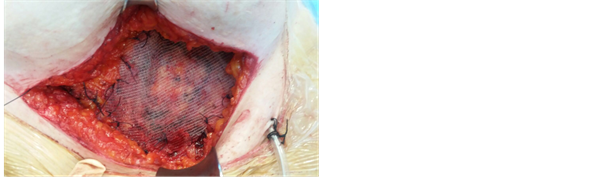

Figure 4. Use of prolene mesh for the abdominal wall defect.

The surgical specimen was then sent for frozen section. After histological confirmation (fibrotic nodule with endometriotic foci) reconstruction of the abdominal wall required prolene mesh grafting for the resulting fascial defect (Figure 4).

The wide excision is the treatment of choice for abdominal wall endometrioma as well as for recurrent lesions [17] . Due to the invasion and adherence to the soft tissue, often reconstruction of the abdominal wall is required, after the wide excision of the mass, using polytetrafluoroethylene (Teflon) patch or polypropylene (Prolene) mesh grafting [4] .